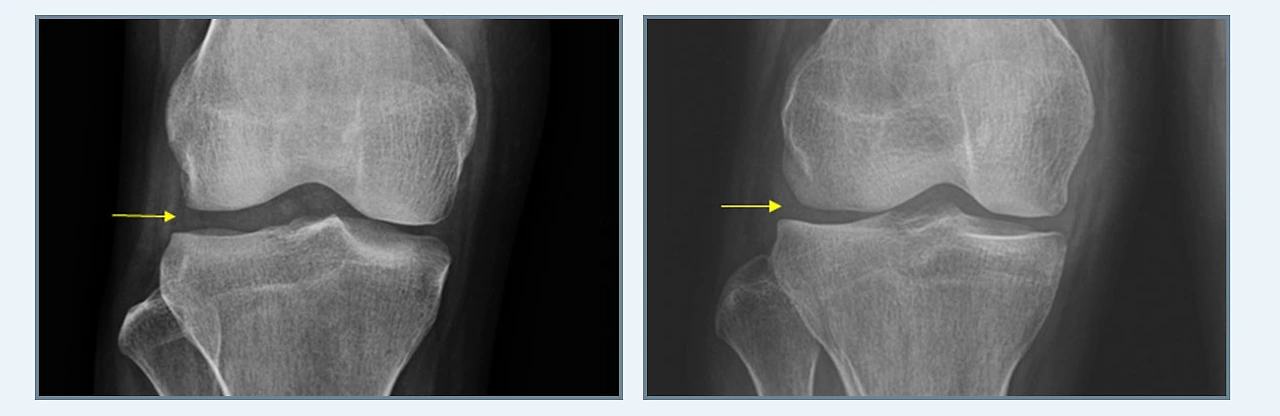

연골판을 봉합해 제 기능을 수행하도록 하는 연골판 봉합술은 크게 후각부 파열과 양동이 손잡이형 파열로 나뉩니다. 연골판의 기능을 보존하기 위해 연골판과 뼈가 부착되어 있는 부분의 가장 후방부인 후각부의 파열을 봉합하는 후각부 파열, 파열부위가 손잡이 젖혀지듯이 움직이기 때문에 관절 사이에 끼어 무릎이 움직이기 힘들어지는 양동이 손잡이형 파열이라고 합니다.

특히 무릎을 구부리는 동작에서 많은 스트레스를 받게 되는 후각부 파열은 생활 습관상 양반다리를 많이 하게 되는 좌식 생활권인 동양권에서 많이 발생합니다. 덧붙여 후각부가 파열되면 연골판의 뿌리가 견고하게 고정되지 않기 때문에 체중이 가해졌을 때 연골판이 고정되지 못하고 밖으로 이탈되는 현상이 발생되어 관절염이 급속하게 진행되기도 한답니다.